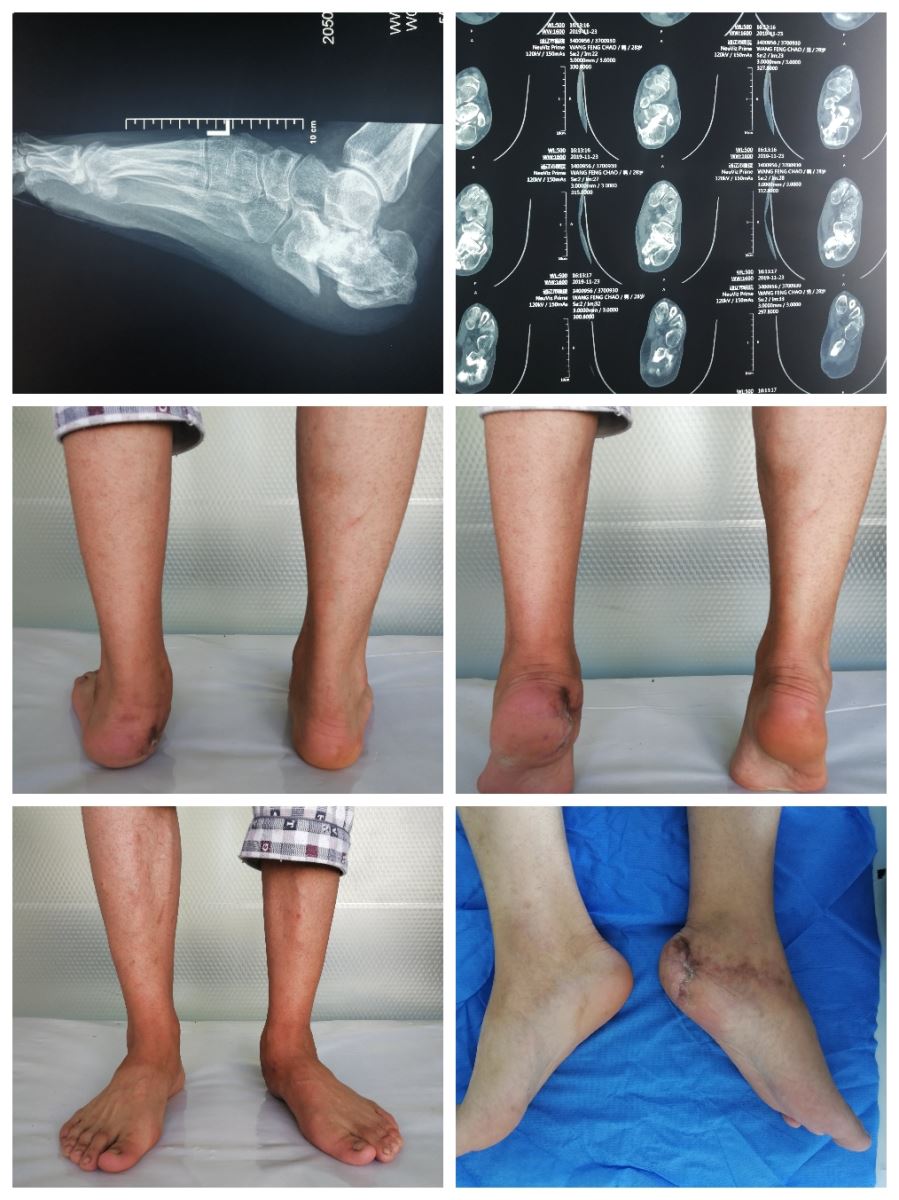

近期我院骨二科成功完成一例跟骨陈旧性骨折的畸形矫正手术。解除了患者的疼痛及心理障碍,填补了我市在跟骨骨折畸形愈合矫形手术治疗方面的空白。患者男性,28岁。一年前左跟骨开放性骨折,于外院仅行克氏针固定,骨折端未予复位。患者下地行走后出现后足疼痛,并出现左下肢外旋畸形,影响美观,对患者心理造成巨大伤害。长距离行走后出现前踝疼痛。患者入院后完善左足ct三位,跟骨侧轴位,双足正侧位。跟骨骨折畸形愈合经常发生大量功能障碍问题,跟骨短缩一方面减少小腿三头肌力臂,使足部跖屈受限。同时距骨后方支持的丢失,亦造成足弓的变平,造成距骨颈和胫骨的撞击,限制踝关节背屈。跟骨后关节面的撕裂可引发创伤性关节炎。跟骨结节骨折块的侧方,头端和前方移位可造成对腓骨(即跟腓撞击)和对腓骨肌腱的直接撞击。跟骨结节移位导致足跟变宽和高度丧失,正常的鞋穿着困难。距下、跟骰和距舟关节的三关节紊乱亦会影响到通过这些关节的多中心运动的协调。跟骨畸形愈合后严重影响患者生活质量,出现步态异常,无法投入到工作中重返社会。通过手术消除疼痛和治疗关节炎,重建后足和中足与踝关节的结构关系就显得非常必要了。

此例患者为Ⅲ型跟骨畸形愈合。在科主任张继锋带领全科共同讨论手术方案后由房芳副主任医师主刀,在肖海祥和陈立福副主任医师协助下,选择可延长的外侧“L”形入路。术中外侧壁骨赘切除,腓侧肌腱粘连松解,行距下关节融合术和跟骨垂直截骨术。显露距下关节清理其内的肉芽组织及关节软骨,直至软骨下骨可见骨面血性渗出。跟腱微创“Z”字形延长。取自体髂骨及混合同种异体骨后植于距下关节。跟骨垂直截骨后内移和下移跟骨结节。分别使用克氏针固定距下关节及截骨面。在C型臂透视下见跟骨力线恢复。跟骨高度恢复。依次拧入4枚空心螺钉固定牢靠。术毕给予患肢中立位石膏外固定。术后患足足弓恢复,外观明显恢复,患者自述左下肢外旋畸形明显改善。患者满意度高。我院骨二科技术力量雄厚,拥有骨科博士、硕士数名,多人有北京积水潭进修经验,业务精湛,以病人为中心。积极开展新技术新项目,精心为通辽市人民的健康提供服务。

术前影像及体位相